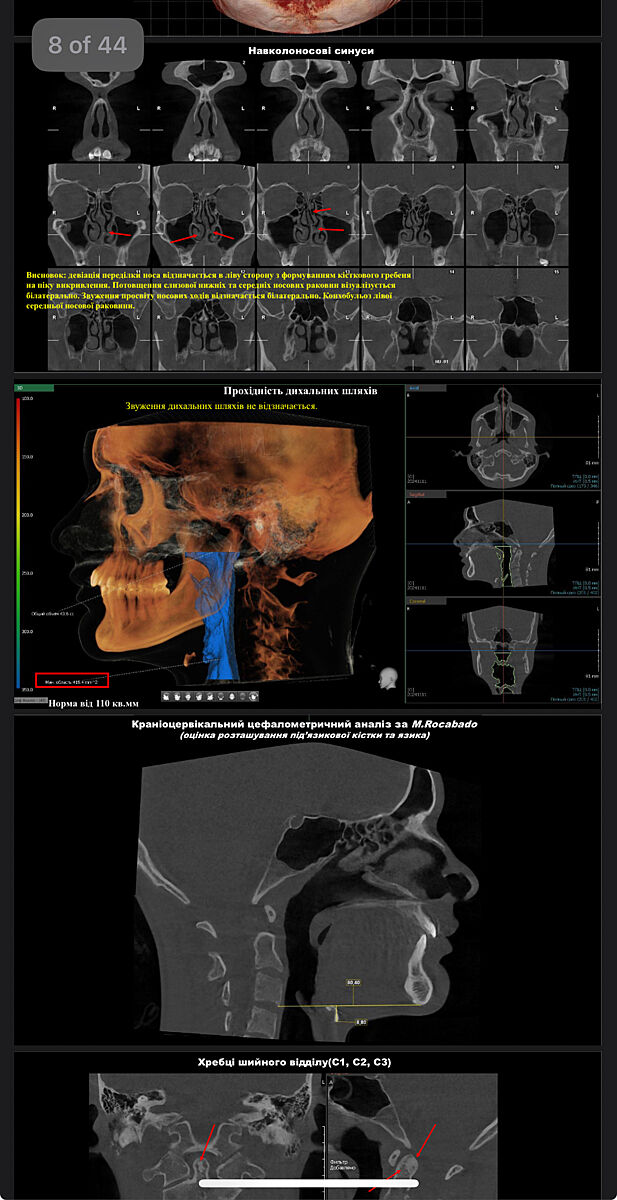

У сына не все так просто , поэтому по максимуму сделали тут . Заграницей уже врач ведет. Вот такое кт